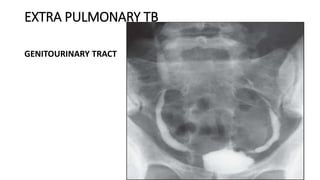

GENITOURINARY TRACT

Nocturia

Frequency

Pyuria

Hematuria

CULTURE NEGATIVE PYURIA

Ureteral Strictures

Hydronephrosis

Infertility